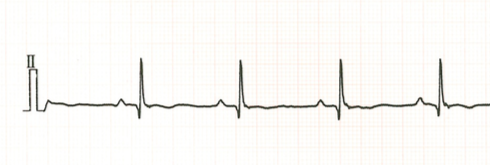

③心電図検査

不整脈や心拡大が存在するかどうかを評価します。

正常な心電図。